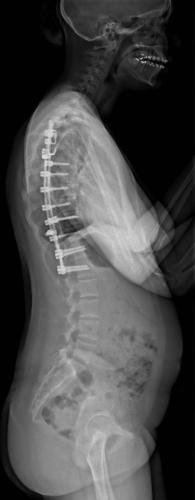

Images de scolioses opérées 16 janvier 202418 janvier 2023 par Damien Scoliose Thoracique 2 Scoliose thoracique Droite - cliché pré-opératoire de Face Scoliose thoracique Droite - cliché pré-opératoire de Profil Scoliose thoracique Droite - cliché post-opératoire de Face Scoliose thoracique Droite - cliché post-opératoire de Profil